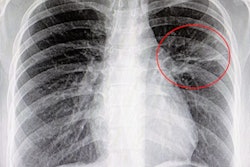

Reveal 35C includes KA Imaging's SpectralDR technology, which images bone and soft tissue images with a single standard x-ray exposure, the company said.